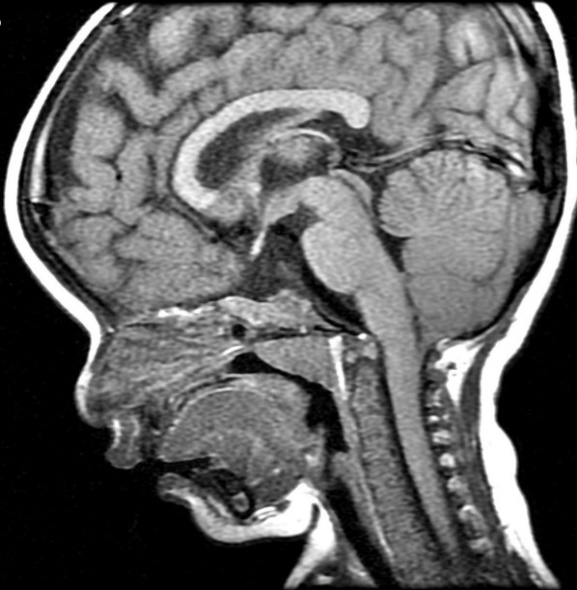

MRI findings showed the lack of the normal flow void of the left internal carotid canal and the first part of the left middle cerebral artery (Figures 1 and 2). The pituitary gland is flat. No evident anterior or posterior pituitary gland tissue or pituitary stalk is observed. The pituitary gland's strong posterior signal is not detected in situ or

ectopic. The left medial cerebral artery originates within the posterior circulation, and the left internal carotid artery cannot be seen. No intra, supra, retro or parasellar masses. Normal MRI appearance of the optic chiasm and corpus callosum. Otherwise, normal MR appearance of the brain parenchyma with no definite focal lesions. Diagnosis of congenital panhypopituitarism associated with agenesis of ICA was made.

a)

b)

c)

d)

Figure 2. a-c) show coronal MRI brain images, and d) is a view in which the left midcranial artery is coming from the posterior circulation and the left internal carotid artery is not visible (agenesis).